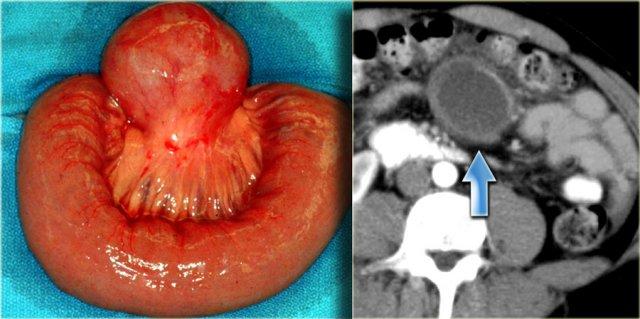

Trường hợp bên trái cũng là u mạch bạch huyết.

Lưu ý rằng CT không phải lúc nào cũng thể hiện rõ các vách ngăn, mặc dù bệnh phẩm cho thấy rõ ràng nhiều vách ngăn.

Siêu âm hoặc MRI mô tả các vách ngăn này tốt hơn CT.

Bên trái là hình ảnh nang ruột đôi.

Nang nằm trong mạc treo đại tràng ngang.

Bệnh nhân này ban đầu được nghi ngờ có khối u tụy dạng nang.

Bệnh phẩm cho thấy đầy đủ các lớp thành ruột.